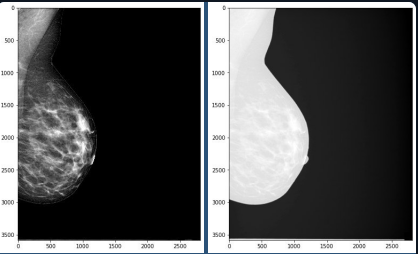

Слева - препроцессинг с VOI LUT, справа - без него